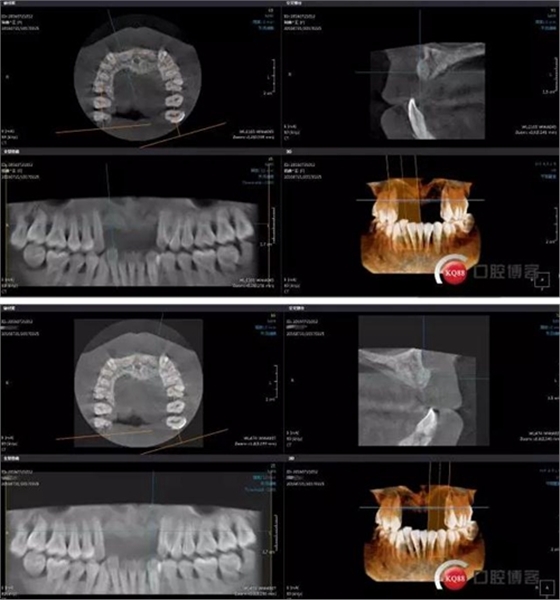

接下來(lái)是GBR五個(gè)月后CBCT,當(dāng)然(1-5月)中間也有拍全景,不一一展示了。

成骨效果尚可,進(jìn)行手術(shù)

前牙區(qū)牙周病骨缺失嚴(yán)重,擔(dān)心成骨效果欠佳先行GBR沒(méi)有同期植入

充分骨整合時(shí)間,植入風(fēng)險(xiǎn)降低且效果穩(wěn)定。